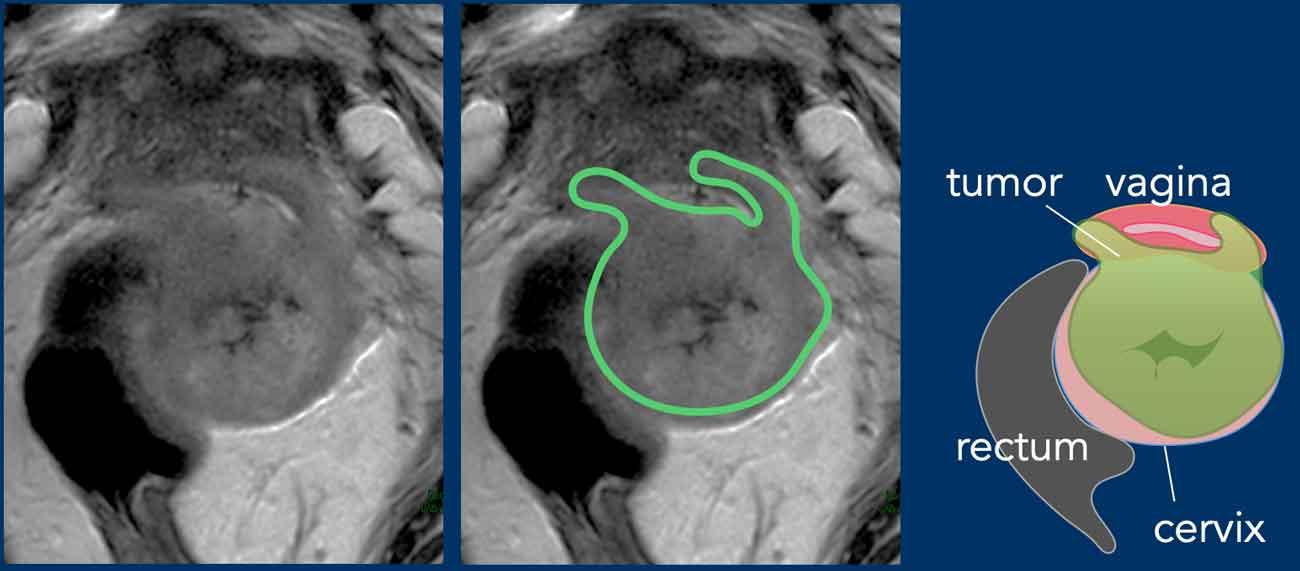

Xâm lấn âm đạo

Xâm lấn thành âm đạo có thể được nhận biết trên MRI chuỗi xung T2W như sự lan rộng của mô mềm tương đối tăng tín hiệu vào trong thành âm đạo.

Trong trường hợp xâm lấn âm đạo, cần xác định xem tổn thương liên quan đến 2/3 trên (giai đoạn IIA) hay 1/3 dưới (giai đoạn III) của âm đạo, vì điều này ảnh hưởng đến xử trí bệnh nhân.

Giai đoạn IIA1/IIA2 có thể đủ điều kiện phẫu thuật ngay từ đầu.

Ngược lại, tổn thương 1/3 dưới âm đạo loại trừ khả năng phẫu thuật và bệnh nhân được chuyển sang hóa xạ trị.